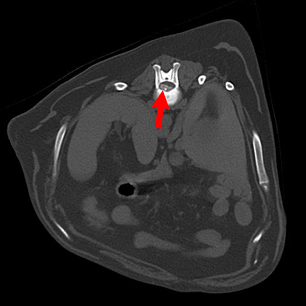

患者の胸腰部CT撮影像

横断面

椎間板物質が脊髄を腹側より圧迫している像を認める